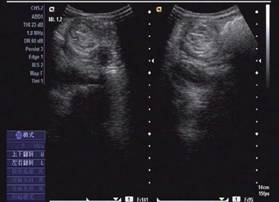

圖示:該患兒當(dāng)時聲像圖表現(xiàn)

超聲圖像表現(xiàn)

1、腸套疊部位顯示邊界清楚的包塊。其橫斷面呈大環(huán)套小環(huán)的特征性表現(xiàn),即“同心圓征”或“靶環(huán)征”。外圓呈均勻的低回聲環(huán)帶,系鞘部腸壁回聲,低回聲帶系水腫增厚的反折壁及其與鞘部之間的少量腸內(nèi)液體形成。在大的外圓內(nèi),又有一個小低回聲環(huán)帶,形成內(nèi)圓。內(nèi)、外圓間為高回聲環(huán),中心部為高回聲團,其邊緣欠光整。套疊部的縱斷面呈“套筒征”或“假腎征”。有時可能顯示套疊的頂部和頸部,頂部呈指頭狀盲端。“假腎征”通常是在套疊時間較長,腸壁發(fā)生嚴(yán)重水腫時出現(xiàn),或是成人患者存在腸管腫瘤或息肉時出現(xiàn)。